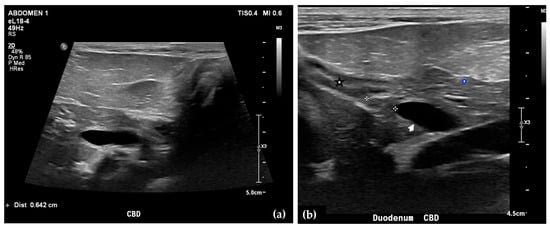

Abdominal radiographs showed no significant abnormalities except a large amount of fecal material in the large intestine. The patient was placed in dorsal recumbency for an abdominal ultrasound (microconvex and linear probes 12–18 MHz, Epiq 5G, Philips Ultrasound, Bothell, WA, USA), with the ventrum shaved from above the xiphoid to the pubis in a roughly square-shaped region. Ultrasound coupling gel and alcohol were used for image optimization. The gallbladder was moderately filled with anechoic fluid and the cystic duct appropriately tapered to the common bile duct (CBD). The CBD could not be traced in its entirety, but the more distal identified segments were multifocally dilated, measuring up to 0.6 cm in diameter (outer wall to outer wall; Figure 1a). At its distal-most aspect, as it approached the duodenal papilla, the CBD abruptly tapered without a discrete intraluminal or extraluminal cause (Figure 1b). Several intrahepatic biliary ducts within the left liver hemisphere were distended distally, measuring up to 0.5 cm in dilation (inner wall to inner wall; Figure 2a,b). No intrahepatic biliary duct dilation of the right hepatic hemisphere was noted. Due to a concern for an unidentified biliary duct obstruction contributing to the patient’s clinical signs/changes, a dual phase contrast abdominal computed tomographic (CT) study was pursued for further evaluation.

Figure 1.

Ultrasound images of the liver. A portion of the common bile duct (CBD) is moderately-markedly distended (between + calipers) (a). Ultrasound image of the duodenum (black-rimmed white star), common bile duct (white arrowhead), and pancreas (blue-rimmed white circle). The distal common bile duct at the level of the duodenal papilla with abrupt narrowing (between calipers) (b).